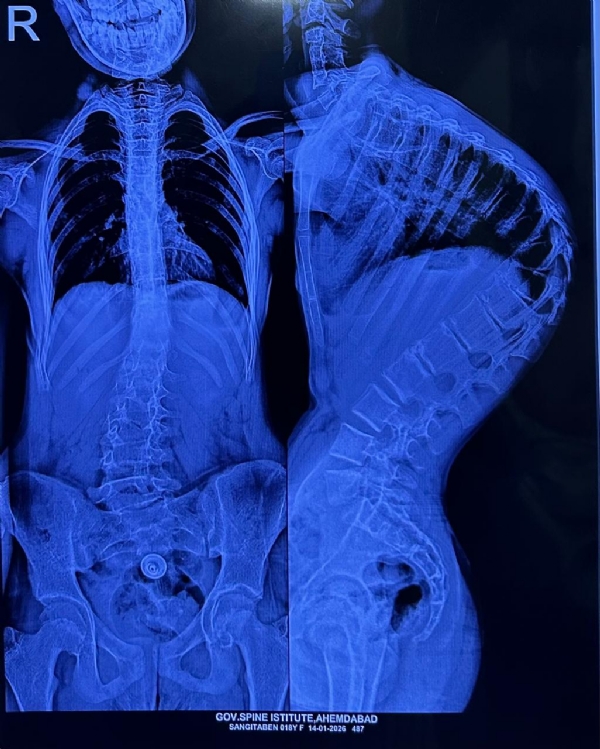

'કાઇફોસ્કોલિયોસિસ' એક ગંભીર બીમારી છે, જેમાં બાળકની કરોડરજ્જુ સાપની જેમ વાંકી વળી જાય છે, તેની સારવાર સામાન્ય મધ્યમ વર્ગ માટે એક સ્વપ્ન સમાન હોય છે. પરંતુ, ઈન્ડો-અમેરિકન સર્જરી કેમ્પના માધ્યમથી આ સ્વપ્ન હકીકત બન્યું છે.

સર્જરીની જટિલતા અંગે ઈન્ડો-અમેરિકન સર્જરી કેમ્પના ડૉક્ટરો જણાવે છે કે, આ એક અત્યંત જટિલ સર્જરી છે. સરેરાશ 4 થી 5 કલાક સુધી ચાલતી આ સર્જરીમાં કરોડરજ્જુને સીધી કરતી વખતે અત્યંત નાજુક ચેતાઓ (Nerves) અને રક્તવાહિનીઓ વચ્ચે કામ કરવાનું હોય છે.

સર્જરી દરમિયાન મુખ્ય પડકાર સતત 'ન્યુરો-મોનિટરિંગ'નો હોય છે. જો કોઈ પણ પગલું ખોટું પડે, તો મુખ્ય રક્તવાહિનીની ઈજાને કારણે દર્દીનો જીવ જઈ શકે છે અથવા જીવનભરનો લકવો (Paralysis) આવી શકે છે. આ જોખમને ખાળવા માટે અમેરિકન ન્યુરો-મોનિટરિંગ ટીમ અને એનેસ્થેસિયા નિષ્ણાતોએ પણ ટેકનિકલ સહયોગ આપ્યો હતો.